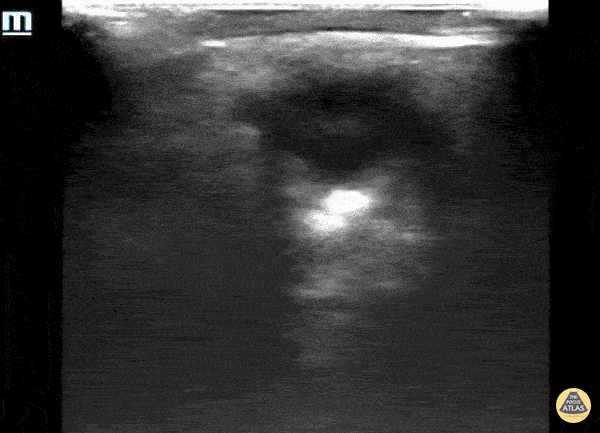

Orbital - Phthisis Bulbi secondary to end stage eye disease

93 year old male with established end stage eye disease found incidentally to have prominent Phthisis Bulbi made evident by a heterogeneous hyper-echoic structures (calcifications) within the posterior chamber of the left eye. Contributed by: Davis, Lindsay; Schlangen, Alex; Welch, Matthew